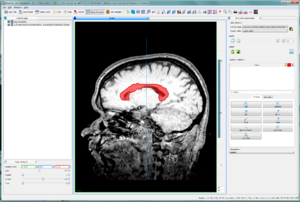

Project Week 25/DICOM Segmentation Support for Cornerstone and OHIF Viewer

Illustrations

Work thus far on segmentations / overlays in Cornerstone